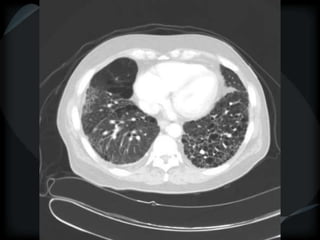

Emphysema - CL

Emphysema - PA

CL + PS emphysema

Hyperlucency

Centrilobular emphysema

Paraseptal emphysema

Panacinar emphysema

CL + PSemphysema